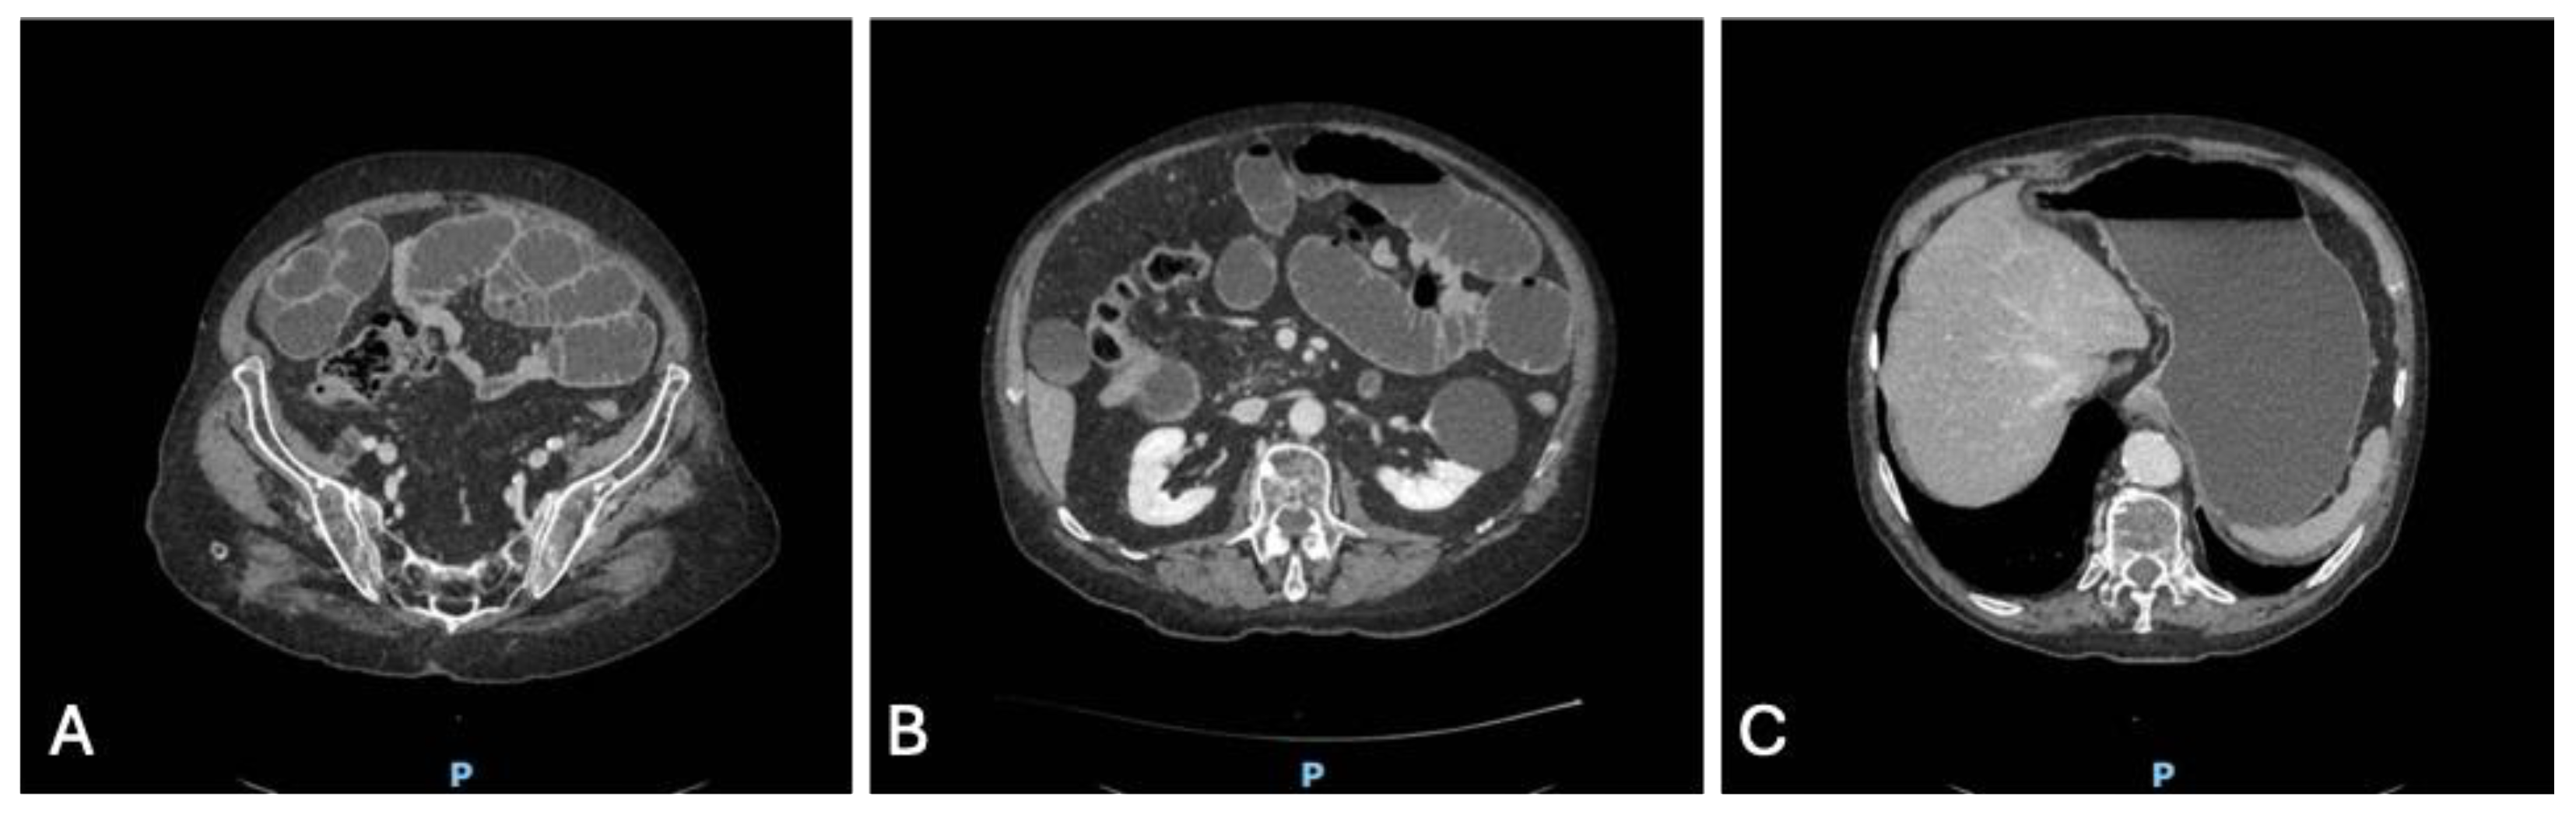

To better delineate the pathology, a contrast-enhanced CT scan of the abdomen was performed. The CT confirmed massive gastric dilatation and diffusely distended ileal loops (Figure 5 A, B, C), with a sharply demarcated transition point and a mesenteric “whirl sign” consistent with a closed-loop obstruction due to volvulus. There was no pneumatosis, portal venous gas, free air, or other radiologic markers of irreversible bowel ischemia.

Figure 5. Axial contrast-enhanced CT images at different abdominal levels showing features of closed-loop small bowel obstruction: (A) dilated ileal loops with air–fluid levels in the lower abdomen and pelvis; (B) central transition point with crowding of mesenteric vessels and a subtle “whirl sign,” consistent with volvulus; (C) markedly distended stomach reaching the subdiaphragmatic region, indicating upstream gastric dilatation due to obstruction.